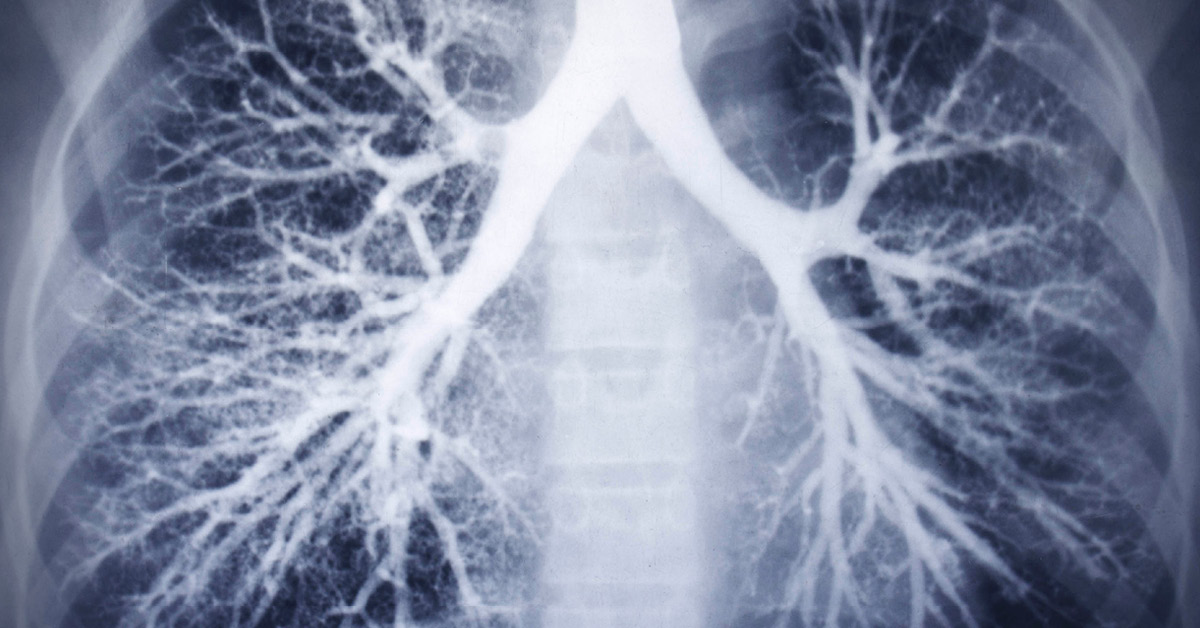

އެމެރިކާގެ މިޝިގަން ސްޓޭޓްގައި ގުނަވަން ބަދަލު ކުރި އަންހެނަކަށް ކޮވިޑު ޖެހިފައިވާ މީހެއްގެ ފުއްޕާމޭ ލެއްވިގެން ކޮވިޑަށް ޕޮޒިޓިވްވެގެން މަރުވެއްޖެއެވެ.

ގުނަވަން ބަދަލު ކުރަން ކުރެވުނު އޮޕަރޭޝަން ކާމިޔާބުވިނަމަވެސް، ކޮރޯނާވައިރަހުގެ އަސަރުކޮށްފައިވާ ފުއްޕާމޭ ލިބުނު މީހާ ވަނީ ކޮވިޑަށް ޕޮޒިޓިވްވެ މިބަލީގައި ހާލުދެރަވެގެން މަރުވެފައެވެ. މިކަމާ ބެހޭގޮތުން ޑޮކްޓަރުން ބުނަނީ އޮޕަރޭޝަން ކުރުމުގެ ކުރިން ދެމީހުންވެސް ކޮވިޑަށް ޓެސްޓު ކުރެވުނު ކަމަށާއި އޮޕަރޭޝަން ކުރިއަށްގެންދެވުނީ ދެމީހުންވެސް ކޮވިޑަށް ނެގަޓިވްވެފައިވުމުންކަމަށެވެ.

މިއޮޕަރޭޝަނުގައި ބޭނުން ކުރެވުނު ޑޮނޭޓް ކޮށްފައިވާ ފުއްޕާމޭގެ ޒަރިއްޔާއިން އޮޕަރޭޝަން ކުރުމުގައި ބައިވެރިވި ޑޮކްޓަރުންނަށްވެސް ކޮރޯނާވައިރަހުގެ އަސަރުކޮށް ކޮވިޑަށް ޕޮޒިޓިވްވި ކަމަށްވެއެވެ. މިއީ އެމެރިކާގައި ގުނަވަނެއް ބަދަލު ކުރި މީހަކަަށް ކޮވިޑް ޖެހުނު ފުރަތަމަ ފަހަރު ކަމަށްވެސް ޔުނިވަރސިޓީ އޮފް މިޗިގަން މެޑިކަލް ސްކޫލުން ހާމަކޮށްފައިވެއެވެ.

މިދިޔަ އަހަރުގެ ތެރޭގައި އެމެރިކާގައި 40،000 މީހުން ގުނަވަން ބަދަލު ކުރުމުގެ އޮޕަރޭޝަން ކުރެވިފައިވާއިރު މިއީ ކޮވިޑުގެ ބަލިމަޑުކަމުގެ ތެރޭގައި ގުނަވަން ބަދަލުކޮށްގެން ކޮރޯނާވައިރަހުގެ އަސަރުކުރިކަމަށް ރިިޕޯޓު ކުރެވުނު ފުރަތަމަ ފަހަރު ކަމަށްވެސް ޔުނިވަރސިޓީ އޮފް މިޗިގަން މެޑިކަލް ސްކޫލުން ހާމަކޮށްފައިވެއެވެ.

ޑޮނޭޓް ކުރި ފުއްޕާމޭ ބޭނުންކުރުމުގެ ކުރިން ކޮވިޑަށް ޕޮޒިޓިވްވިނަމަ އެފުއްޕާމޭ ބޭނުން ނުކުރާނޭކަމަށްވެސް ޑޮކްޓަރުން ވަނީ ބުނެފައެވެ.

އިންސާނުންނަށް ކޮރޯނާވައިރަހުގެ އަސަރު ކޮށްފައިވާކަން ޓެސްޓުތަކުން ގިނަ ފަހަރަށް އެނގެނީ ވަކި މުއްދަތެއްްގެ ފަހުންކަމަށް ދިރާސާތަކުން ދައްކައެވެ. ވީމާ ގުނަވަން ބަދަލު ކުރުމަށް ބޭނުން ކުރެވުނު ފުއްޕާމޭގައި ވައިރަހުގެ އަސަރު ކިތަންމެ ކުޑަކޮށް ހުއްޓަސް ވައިރަސް ދިރިހުރުމަށް ފުރުސަތުލިބި، ވައިރަސް ފެތުރި ކޮވިޑަށް ޕޮޒިޓިވްވުމަކީ އެކަށީގެންވާ ކަމެއްކަމަށް ޑޮކްޓަރުން ވަނީ ބުނެފައެވެ.